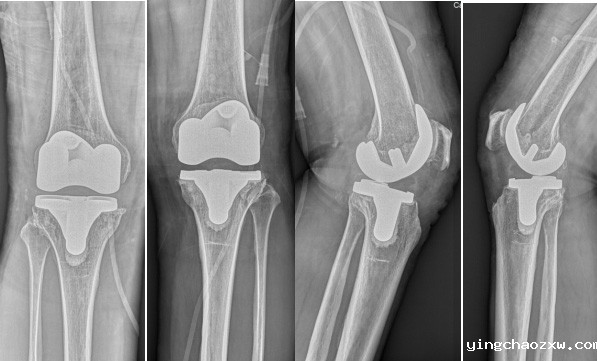

据悉,该患者为女性,现年55岁,双膝关节反复疼痛已有10余年,并伴有膝关节肿胀,膝关节屈曲活动受限,不能下蹲,上下楼非常困难。期间患者曾辗转多家外院进行治疗,均未见好转。患者入院后,骨伤科医疗团队完善相关检查,明确患者为双膝关节退行性病变。考虑到患者双膝关节炎病史较长,膝关节退变严重,膝关节已磨损软骨无法恢复,如继续采用保守治疗,效果并不理想,患者仍将长期忍受疼痛的折磨,严重影响生活质量。为了消除患者的痛苦,让患者早日恢复健康,骨伤科医疗团队综合研究患者病情,制定了科学、合理、安全、有效的治疗方案,于11月16日对患者实施了双膝内轴型人工关节置换术。术后患者膝关节疼痛消除,手术结束患者即可自行抬腿,屈伸膝关节,术后第二日无需持拐杖就可下床行走,手术获得圆满成功。

膝关节骨性关节炎是中老年人的一种常见关节疾病,它是由关节软骨磨损退化病变所致,给中老年人带来痛苦和磨难,甚至造成残疾。在我国,60岁以上的老年人有78.5%以上患有膝关节骨性关节炎。随着人口老龄化的不断加剧,膝关节退行性关节炎等疾病的发生率呈逐步上升趋势。数据显示,2022年国内全膝关节置换手术量预计达44.2万例。同时,有研究指出,近20%的患者对全膝关节置换的手术效果并不满意,其主要原因是术后膝关节出现不稳定情况。内轴型膝关节设计无需进行髁间截骨,通过手术医生对软组织的毫米级精准平衡,在极高的骨保留基础上提供更高的关节活动度以及更可靠的耐磨性能,尽可能地模仿自然膝关节的运动特征以重建膝关节正常的运动力学,维持膝关节在运动中的稳定性,使得术后的运动力学特征和患者步态更加自然,使患者术后感受更好,几乎“忘记”换过膝关节,进一步提高了患者的满意度。临床随访17年的结果显示内轴型膝关节具有极高的假体存留率(98.8%)和患者满意度(95%)。